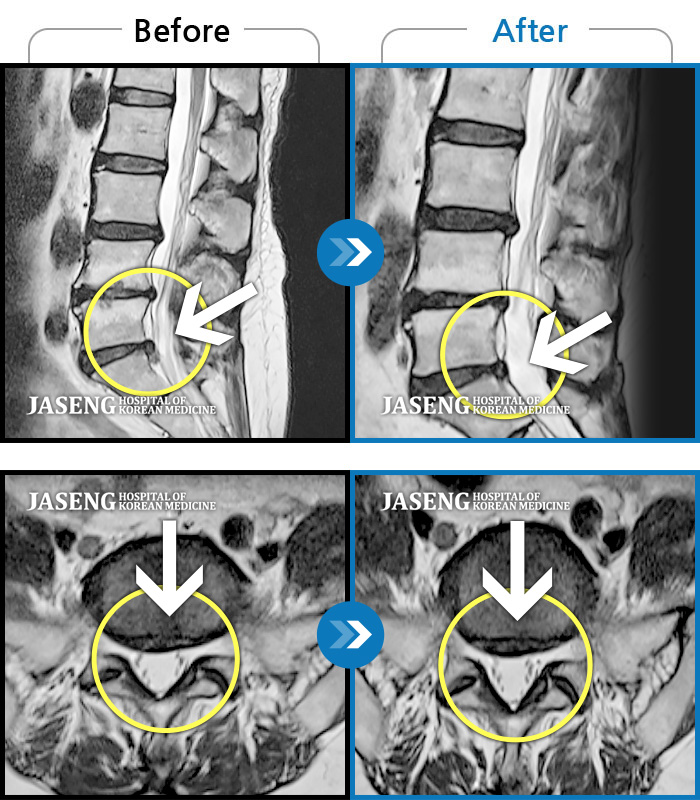

MRI 치료사례

좌측 하지 및 골반 방사통 및 저림증상